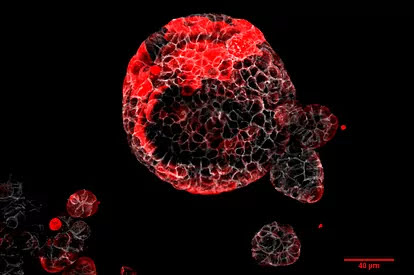

“Este desconocimiento se ha traducido en una falta de terapias efectivas para eliminar la enfermedad residual y evitar la recurrencia metastásica que tienen un mal pronóstico. Con este trabajo se han podido identificar por primera vez células tumorales residuales ocultas en el hígado y pulmón y han caracterizado cómo evolucionan hasta dar lugar a la aparición de metástasis en estos órganos”.

Pero en entre un 20% y un 35%, el cáncer reaparece en otros órganos vitales en forma de metástasis. Éstas se originan por células tumorales residuales que permanecen ocultas en el momento de la cirugía, principalmente en el hígado o el pulmón. Las metástasis son la principal causa de muerte de casi todos los tipos de cáncer, incluido el de colon.